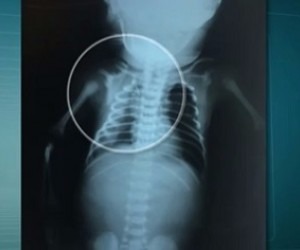

Morreu neste domingo (30), o bebê Arthur, que foi baleado na barriga da mãe em Duque de Caxias, na Baixada Fluminense. De acordo com a Secretaria estadual de Saúde, o bebê morreu às 14h05. O quadro clínico piorou em decorrência de uma hemorragia nesta madrugada.

Laudo médico indicou que Arthur ficaria paraplégico por conta da lesão causada pelo tiro.